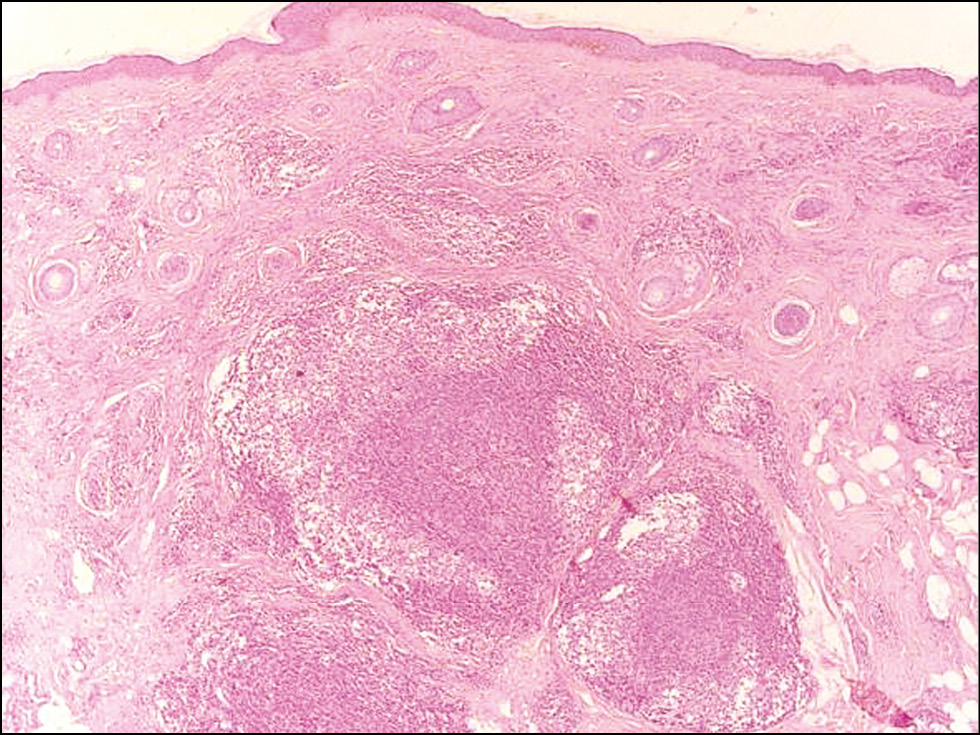

Изучение патоморфологических особенностей ДЛК позволило выделить её основные черты. Лимфоцитарный инфильтрат, состоящий преимущественно из малых В-лимфоцитов, плазматических клеток, гистиоцитов, макрофагов, нейтрофильных и эозинофильных форм гранулоцитов, в большинстве случаев располагался в верхних (n=16; 53%) и средних (n=11; 36,7%) слоях дермы, однако при ДЛК, представленной узлами (n=3; 10%), он распространялся и на подкожно-жировую клетчатку (рис. 6). Во всех случаях наблюдалась сохранность придатков кожи с перифокальными инфильтратами, а также пролиферация микрососудов (рис. 7). Из 30 больных ДЛК у 8 (26,7%) в коже были обнаружены фолликулоподобные структуры (рис. 8), у 6 (20%) ― лимфоидные фолликулы с герминативными центрами (рис. 9). Лимфоидные фолликулы различных размеров имели характерные чёткие границы с широким ободком из мелких лимфоцитов. В герминативном центре лимфоидных фолликулов наблюдались многочисленные митозы. При иммуногистохимическом исследовании кожи в биоптатах всех больных ДЛК в дермальном инфильтрате было выявлено преобладание CD20+ В-лимфоцитов (рис. 10) Соотношение IgL κ/λ составило примерно 1:1 во всех биоптатах (рис. 11, 12). По результатам ПЦР-анализа: по реаранжировкам генов IgH B-клеточная клональность не выявлялась в большинстве случаев (n=25; 83%), в 5 (17%) ― результат был интерпретирован как сомнительный.

Рис. 8. Патоморфологические особенности доброкачественной лимфоплазии кожи: эпидермис и придатки кожи не повреждены; в средних, глубоких отделах дермы и подкожно-жировой клетчатке определяется очаговая лимфоидная инфильтрация с формированием фолликулоподобных структур с герминативными центрами, ×50. / Fig. 8. Pathomorphological features of benign lymphoplasia of the skin: the epidermis and appendages of the skin are not damaged. Focal lymphoid infiltration with the formation of follicle-like structures with germinative centers is determined in the middle, deep parts of the dermis and in subcutaneous adipose tissue, ×50.

Рис. 9. Патоморфологические особенности доброкачественной лимфоплазии кожи: очагово-диффузная инфильтрация лимфоидными клетками в глубоких слоях дермы с формированием множественных вторичных лимфоидных фолликулов с герминативными центрами, ×50. / Fig. 9. Pathomorphological features of benign lymphoplasia of the skin: focal-diffuse infiltration by lymphoid cells in the deep layers of the dermis with the formation of multiple secondary lymphoid follicles with germinative centers, ×50.